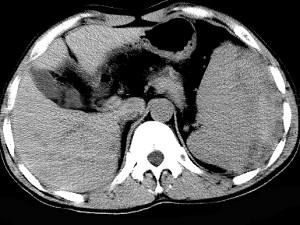

男、52岁1小时前车祸,伤及左季肋区,CT扫描如图,最可能的诊断是 ( )A、脾脓肿B、脾淋巴瘤C、脾破裂D、脾血管瘤E、脾梗死

问题 男、52岁1小时前车祸,伤及左季肋区,CT扫描如图,最可能的诊断是 ( )

选项 A、脾脓肿 B、脾淋巴瘤 C、脾破裂 D、脾血管瘤 E、脾梗死

答案 C